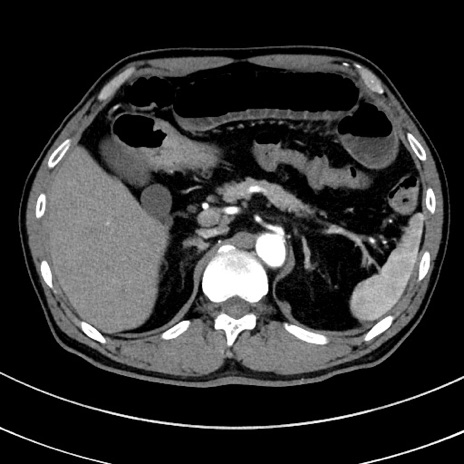

症例8(横断像)

【症例】 60歳代男性

【主訴】 黒色吐物

【現病歴】 4日前から嘔気自覚、2日前の朝食後にも嘔気あり、自分で手で嘔吐反射起こし嘔吐したところ血が混ざっていたため受診。

【既往歴】 5年前汎発性腹膜炎を伴う急性虫垂炎で手術、高血圧、前立腺肥大症、高脂血症

【身体所見】 腹部正中に手術癩痕あり 腹部平坦・軟圧痛なし膨満感あり

【データ】WBC 8400、CRP 4.54